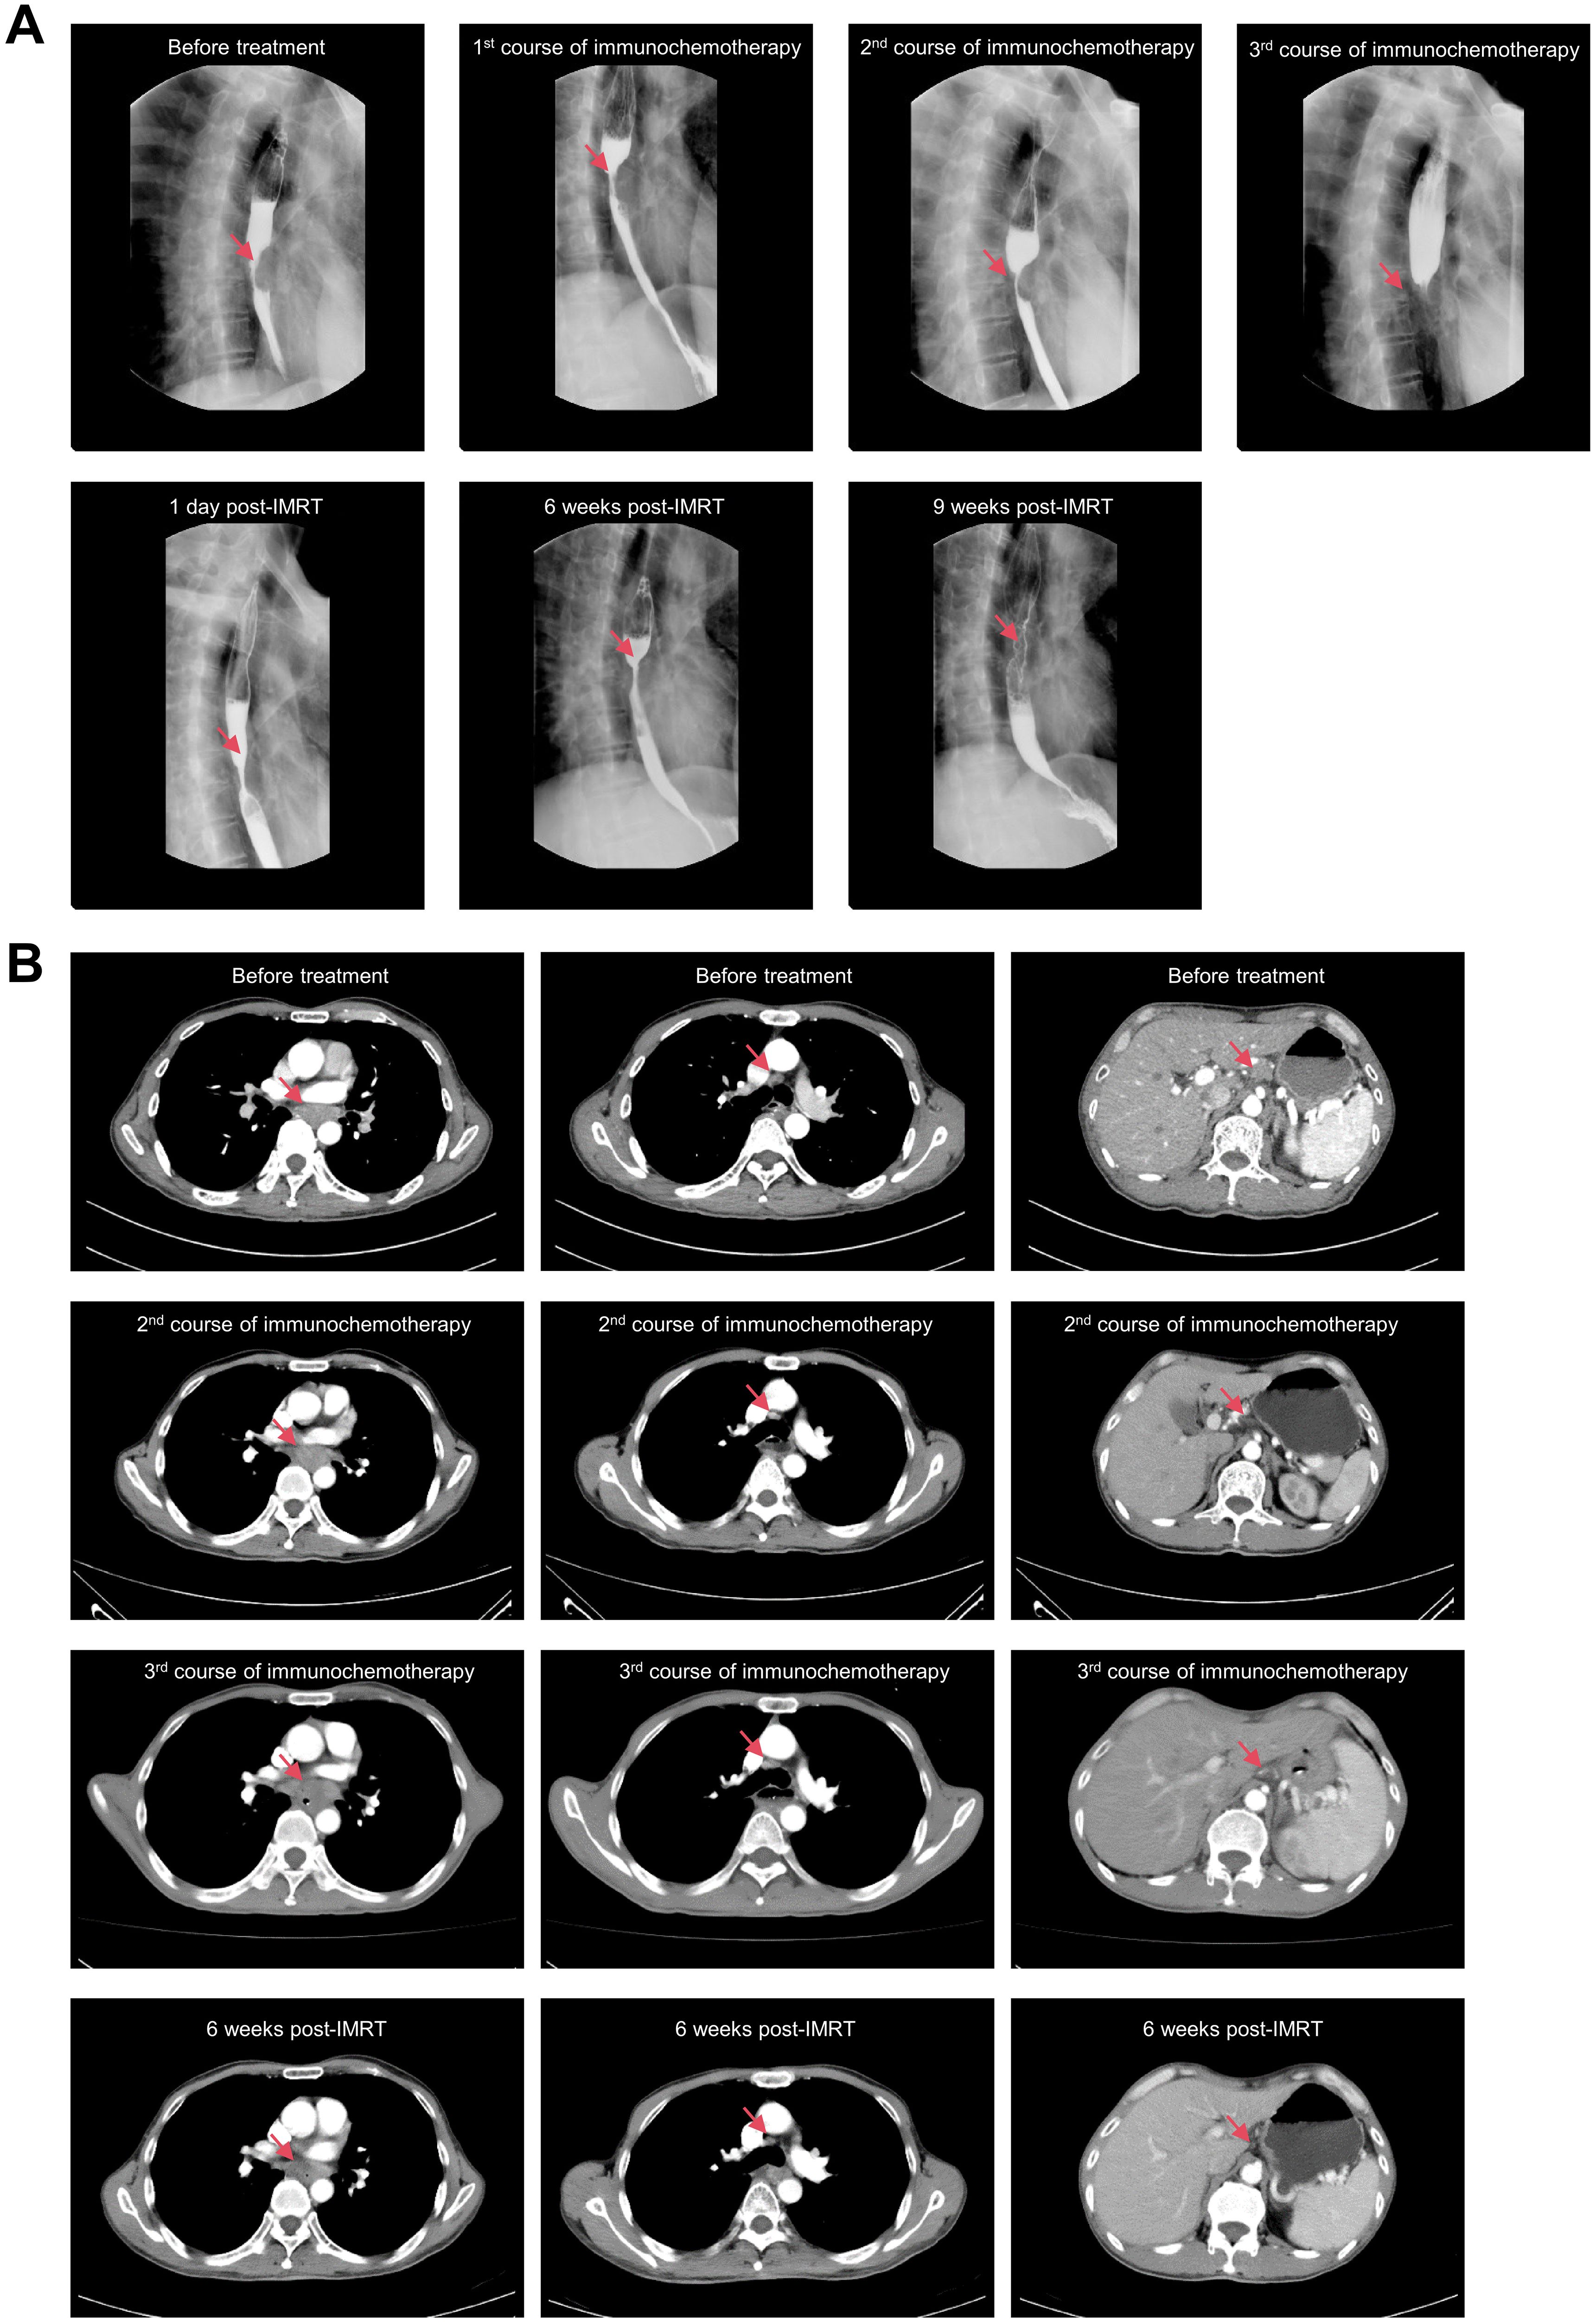

Esophageal cancer exhibits a high incidence in the Chaoshan region of south China, an area characterized by distinctive dietary habits prominently featuring the consumption of preserved pickles and hot tea. Common metastatic sites of esophageal cancer include the lungs, liver, brains, and bones, while occurrence in the distal ends of the limbs is exceptionally rare. Here we present a case of a 62-year-old man from China's Chaoshan region presented with progressive right ring finger pain, swelling, and gangrene. After the amputation of digit, histopathology unexpectedly identified well-differentiated esophageal squamous cell carcinoma (ESCC) with positive margins. A comprehensive retrospective evaluation of medical history identified previously undocumented intermittent dysphagia and mild thoracodorsal pain, postdating the initial presentation of digital symptom by one months. The Esophageal Cancer Multidisciplinary Team confirmed the diagnosis of mid-thoracic ESCC at stage T4bN2M1 according to the AJCC(The American Joint Committee on Cancer, AJCC)8th edition criteria based on further examinations. Following a multidisciplinary approach encompassing digital amputation, immunochemotherapy, and localized radiotherapy to the primary lesion, the disease achieved partial response according to RECIST(Response Evaluation Criteria in Solid Tumors, RECIST)1.1 criteria.This case highlights the diagnostic challenges of rare metastatic presentations in ESCC, and the critical importance of recognizing atypical symptoms in high-risk populations. Early multidisciplinary intervention may improve outcomes in rare oligometastatic disease .